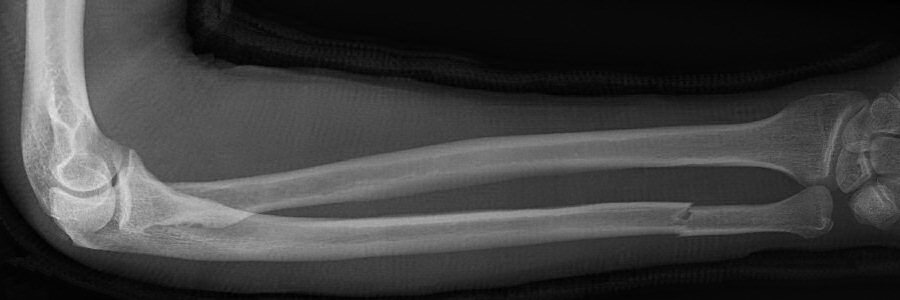

Monteggiafraktur: fraktur på ulna och samtidig luxation av caput radii. Man är inte helt överens om ulnafrakturen ska vara i den proximala tredjedelen eller proximala två tredjedelarna av ulna. Radiushuvudet kan också vara frakturerat istället för luxerat.

Monteggiafraktur